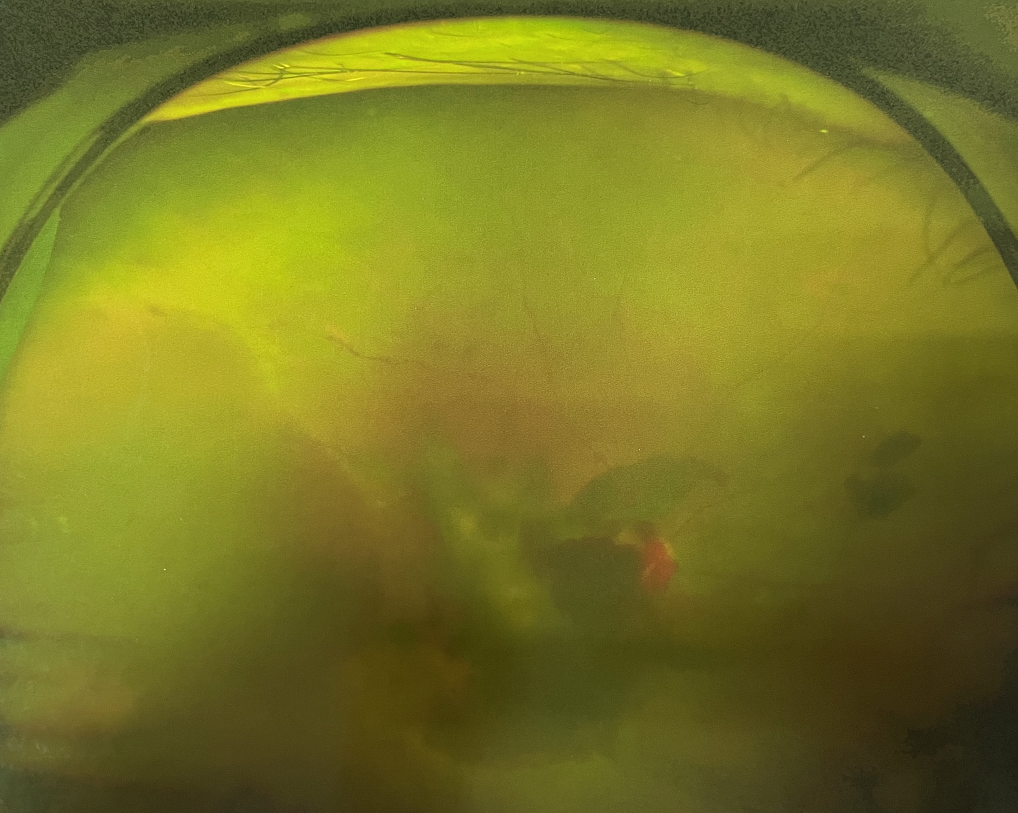

眼底出血

1、眼底出血

高血壓、糖尿病、動脈粥樣硬化、高度近視、視網(wǎng)膜中央靜脈阻塞、脈絡(luò)膜新生血管性疾病等都可能造成眼底出血,引起中心視力下降、視物變形、黑影飄動、飛蚊癥、閃光感等癥狀。